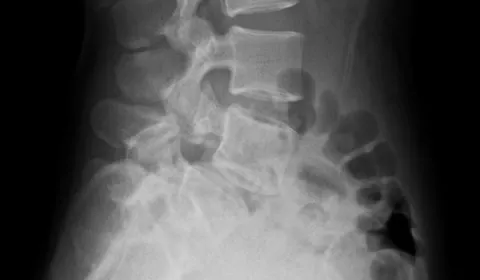

【案例】椎弓骨折

作者:王思恒

2021-04-12 16:58:00

30歲出頭的女子剛開始重訓沒多久,在一次硬舉之後開始感到下背疼痛。原本以為春節假期休息一下就會好,沒想到疼痛一直持續。